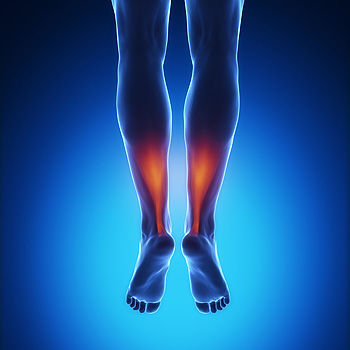

Achilles Tendon Injury Symptoms

The Achilles tendon is a band of tissue that connects the muscles in your calf to your heel. Injuries to this tissue can be common, especially among athletes. The typical symptoms of an Achilles tendon injury can include pain down the back of your leg near your heel, pain that worsens with activity, stiffness or soreness in the Achilles tendon upon waking, pain in the tendon the day after exercising, swelling that worsens with activity, thickening of the tendon, bone spurs on the heel bone, and difficulty flexing the affected foot. If you are injured and hear a popping sound, followed by a sudden, sharp pain, this could be indicative of an Achilles tendon rupture. If you are experiencing any of these symptoms, please consult with a podiatrist.

What Is the Achilles Tendon?

The Achilles tendon is a tendon that connects the lower leg muscles and calf to the heel of the foot. It is the strongest tendon in the human body and is essential for making movement possible. Because this tendon is such an integral part of the body, any injuries to it can create immense difficulties and should immediately be presented to a doctor.

What Are the Symptoms of an Achilles Tendon Injury?

There are various types of injuries that can affect the Achilles tendon. The two most common injuries are Achilles tendinitis and ruptures of the tendon.

Achilles Tendinitis Symptoms

- Inflammation

- Dull to severe pain

- Increased blood flow to the tendon

- Thickening of the tendon

Rupture Symptoms

- Extreme pain and swelling in the foot

- Total immobility

Treatment and Prevention

Achilles tendon injuries are diagnosed by a thorough physical evaluation, which can include an MRI. Treatment involves rest, physical therapy, and in some cases, surgery. However, various preventative measures can be taken to avoid these injuries, such as:

- Thorough stretching of the tendon before and after exercise

- Strengthening exercises like calf raises, squats, leg curls, leg extensions, leg raises, lunges, and leg presses